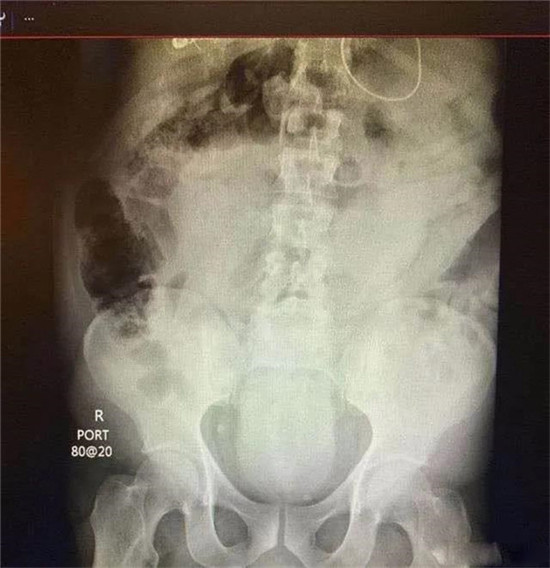

医生给他检查的时候,发现已经有腹膜炎症状,怀疑肠梗阻,拍了个片子,就是上面那个片子:一条大黄鳝在肚子里。

考虑到他已经有腹膜炎的症状,说明肠子已经有个地方破了。只能动手术了。

把肚子打开后,发现大肠破了个洞,黄鳝的头,就在那个洞里。他肚子里都是大便。他的肠子水肿很厉害。黄鳝堵住了大肠,肠梗阻,导致大肠坏死穿孔了。